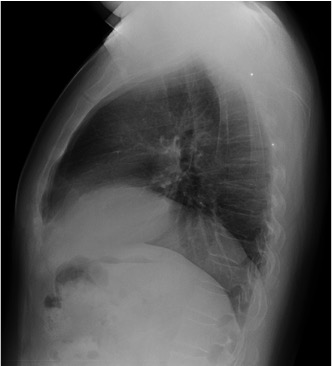

CASO: Febrícula y tos de 4 días de evolución.

Hallazgos:

- En la placa PA se observa una asimetría en los hilios pulmonares, el hilio izquierdo tiene una densidad aumentada.

- Tras examinar la placa lateral se observa un aumento de densidad en la columna que puede ser compatible con una condensación, es el signo de la desnificación vertebral.

SIGNO DE LA DENSIFICACIÓN VERTEBRAL: En la radiografía lateral normal, la densidad de la columna torácica tiende a disminuir desde la parte superior hasta el diafragma; la alteración de ese patrón por la presencia de una densidad superpuesta a la columna, indica la existencia de una consolidación pulmonar. Este signo adquiere especial valor cuando en la proyección posteroanterior la consolidación está oculta en el espacio retrocardíaco o en la base pulmonar.